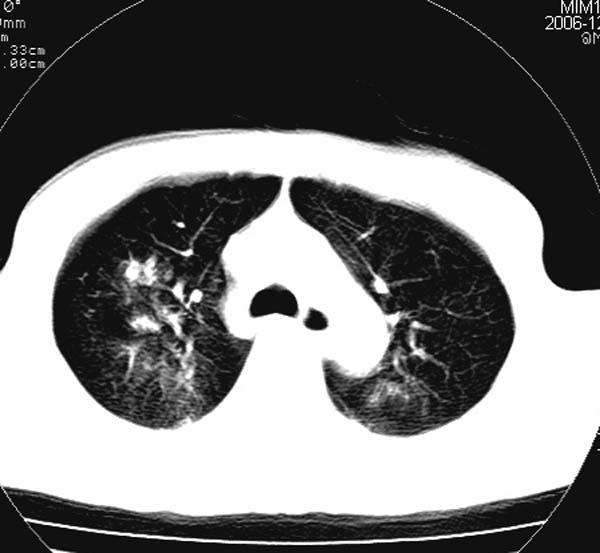

此病人是摔伤后12小时,38岁,无结核病史。谢谢

对不起各位,学着发图片,所以没有发全。此病人是摔伤后12小时,38岁,无结核病史。谢谢!

影像必须密切结合临床!此病例首先考虑肺撕裂伤,间质性改变为主,右侧有创伤性湿肺表现。鉴别诊断诸位大虾已经说得非常ok了。

结合病史,考虑肺挫伤可能,双侧少量胸腔积液.建议短期复查.

影像必须密切结合临床!此病例首先考虑肺撕裂伤,间质性改变为主,右侧有创伤性湿肺表现。鉴别诊断诸位已经说了。

此病例首先考虑肺撕裂伤,间质性改变为主,右侧有创伤性湿肺表现,可短期治疗复查。